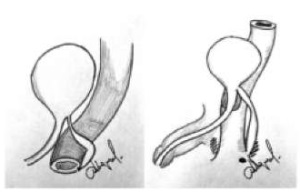

Удвоение уретры — редкий врожденный порок развития нижних мочевых путей, в подавляющем большинстве случаев характерен для мальчиков. Истинная частота встречаемости неизвестна, публикации в медицинских сообществах малочисленны, как правило, представлены отдельными клиническими наблюдениями. Удвоения уретры подразделяют на полное (обе уретры выходят отдельно из мочевого пузыря и открываются каждая своим меатусом) и неполное (добавочный канал имеет только одно отверстие: в дистальном отделе на поверхности полового члена или в проксимальном отделе, сообщаясь с основной уретрой). Неполное удвоение уретры встречается чаще. Вариабельность и частота клинических проявлений определяется типом аномалии и наличием осложнений. Верификация варианта удвоения при наличии удвоенного меатуса, деформации полового члена и двойной струи мочи не вызывает затруднений. Клинические варианты, сопровождающиеся дизурическими явлениями, рецидивирующей инфекцией мочевыводящих путей, недержанием мочи или клиникой парапроктита, встречаются значительно реже и могут вызывать трудности в своевременной диагностике. Удвоения уретры, представленные наличием парауретерального хода, могут сопровождаться отсутствием симптоматики в течение длительного времени. Дополнительные сложности связаны с отсутствием общепринятой утвержденной классификации, алгоритмов диагностики и тактики хирургического лечения, что ставит перед детскими хирургами и урологами серьезные задачи при лечении данной патологии. Большинство специалистов опирается, как правило, на классификацию удвоения уретры E.L. Effman (1976) и/или Williams — Kenawi and Mollard (1984). Мы использовали классификацию E.L. Effman (1976), которая считается наиболее полной и детализированной, именно ее мы использовали при описании клинических наблюдений в данной статье.

Хирургическое лечение зависит от классификационного типа и включает, как правило, иссечение добавочной уретры и пластику основной уретры при необходимости. Лечение подтипа IIA2-Y представляет наибольшие технические сложности, поскольку требует пластики промежности, иссечения второй уретры и восстановления анатомии мочеиспускательного канала.

В данной статье представлены IIA2-Y типы удвоения уретры у мальчиков.